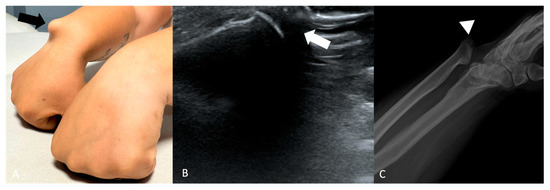

A bony bump (Figure 5) may represent the consequence of a traumatic event (most common) or be due to underlying developmental anomalies. Hand and wrist injuries constitute 6.6% to 28.6% of all injuries in the musculoskeletal system. The most affected anatomical region of the upper extremity is the fingers (38.4%), followed by the wrists (15.2%) [26].

Figure 5.

(A) Physical examination of a 27-year-old female shows a bump deformity on the medial side at the level of the radio-ulno-carpal joint (black arrow). (B) US shows the presence of abnormal bone (white arrow). (C) X-rays reveal a severe radioulnar-carpal joint deformity with dorsal ulnar metaepiphysis luxation in fracture outcomes (arrowhead).

In case of a suspicious bony lesion, X-ray is the modality of choice and often allows the diagnosis without the need for other imaging modalities [27]. CT is particularly useful for assessing occult osseous abnormalities, such as undisplaced fractures, subtle subluxations, erosions, and osteolytic lesions [28]. On the other hand, MRI is the modality of choice for evaluating soft tissues—including the articular capsule, ligaments, fibrocartilage, tendons, and muscular attachments around the joint. It provides excellent visualization of capsuloligamentous injuries, from mild sprains to complete tears. MRI is also ideal for detecting occult fractures, bone marrow edema due to trauma, inflammation or infection, and early erosive changes [29].